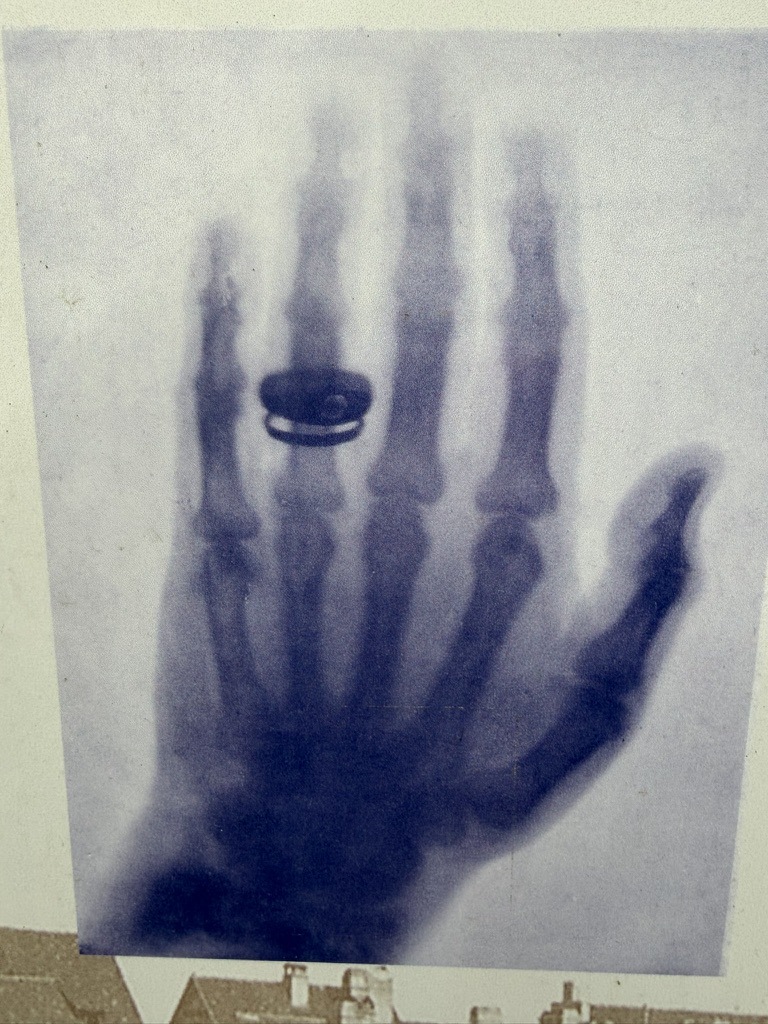

saw this organ donation poster…